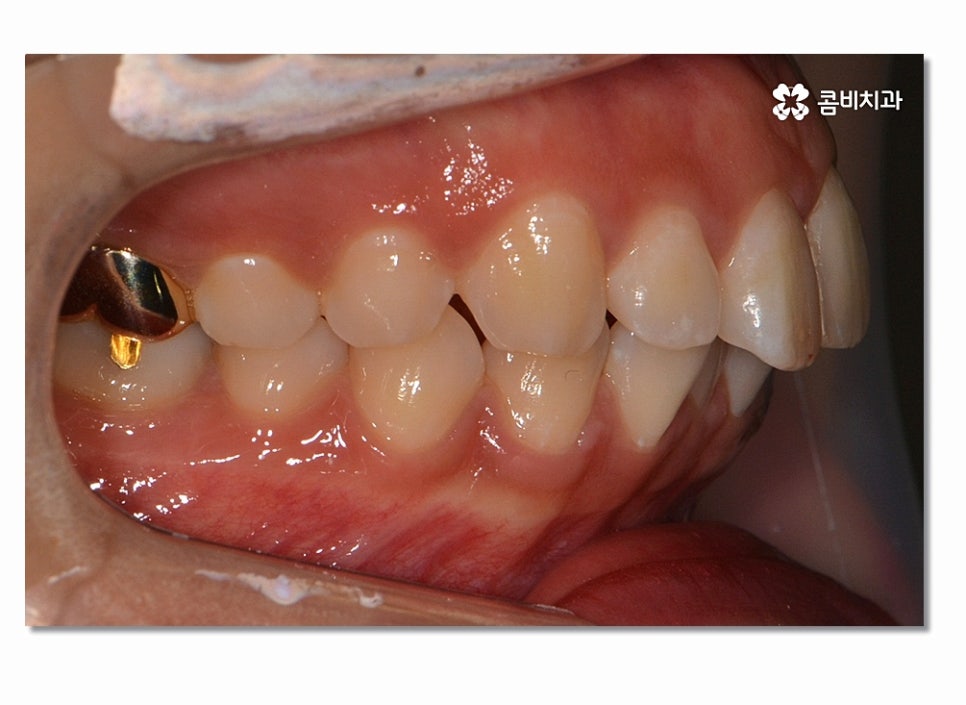

돌출입치아교정이 시작되면 이처럼 전방으로 뻐드러진

앞니를 시간이 지남에 따라서 후방으로 이동시키면서 돌출입이

점점 개선되며 이러한 치열의 변화는 교합도 잘 맞물리도록

신경 써야 하며 얼굴 변화에 대한 부분까지 잘 생각해야 할 수 있어요.

위 사진을 보시면 치아교정 과정을 통해서 치열의 가지런함은 물론이며

측면에서 보더라도 돌출입이 많이 개선된 것을 느낄 수 있을 거예요.